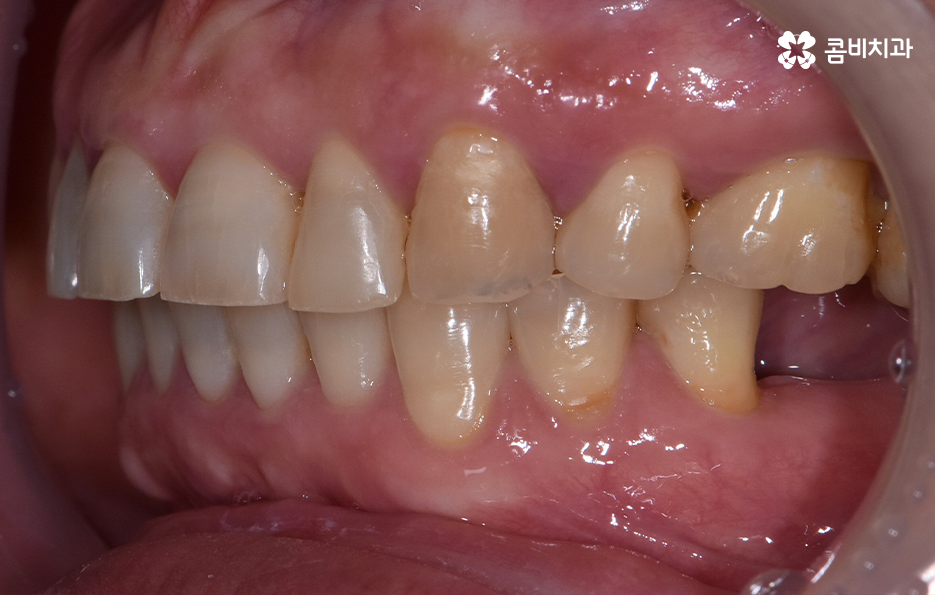

특히 치아가 벌어지거나 삐뚤한 경우에는 임플란트 시술만 한다고 가정할 때 기존의 치열에서 교합 관계 위주로 임플란트의 식립 각도와 위치, 보철물의 크기 등을 결정하게 되지만 치아교정을 통해 가지런한 치열로 개선한 후에 임플란트를 식립하는 경우에는 가지런한 치열을 갖춘 상태에 적합한 임플란트 치료 계획을 세운다는 점에서 이점이 있어요

오늘 보시는 포스팅에서의 치료 과정도 어금니에 임플란트가 필요한 상태에서 윗니를 보시면 윗니가 다소 벌어진 것을 확인할 수 있는데요. 교정 하면 보통 전체교정을 떠올리게 되긴 하지만 경우에 따라서는 치열이 전체적으로 가지런한 편인데 앞니가 살짝 벌어진 경우나 어금니만 다소 벌어진 경우도 있을 거예요

이러한 경우에는 부분교정을 통해서 다소 개선이 필요한 치열을 가지런하게 만들고 가지런해진 치열과 교합 상태에 적합한 임플란트 치료 계획을 세워서 치아의 심미성과 기능적인 부분, 얼굴과의 조화를 종합적으로 고려하여 좋은 결과를 얻을 수 있어요